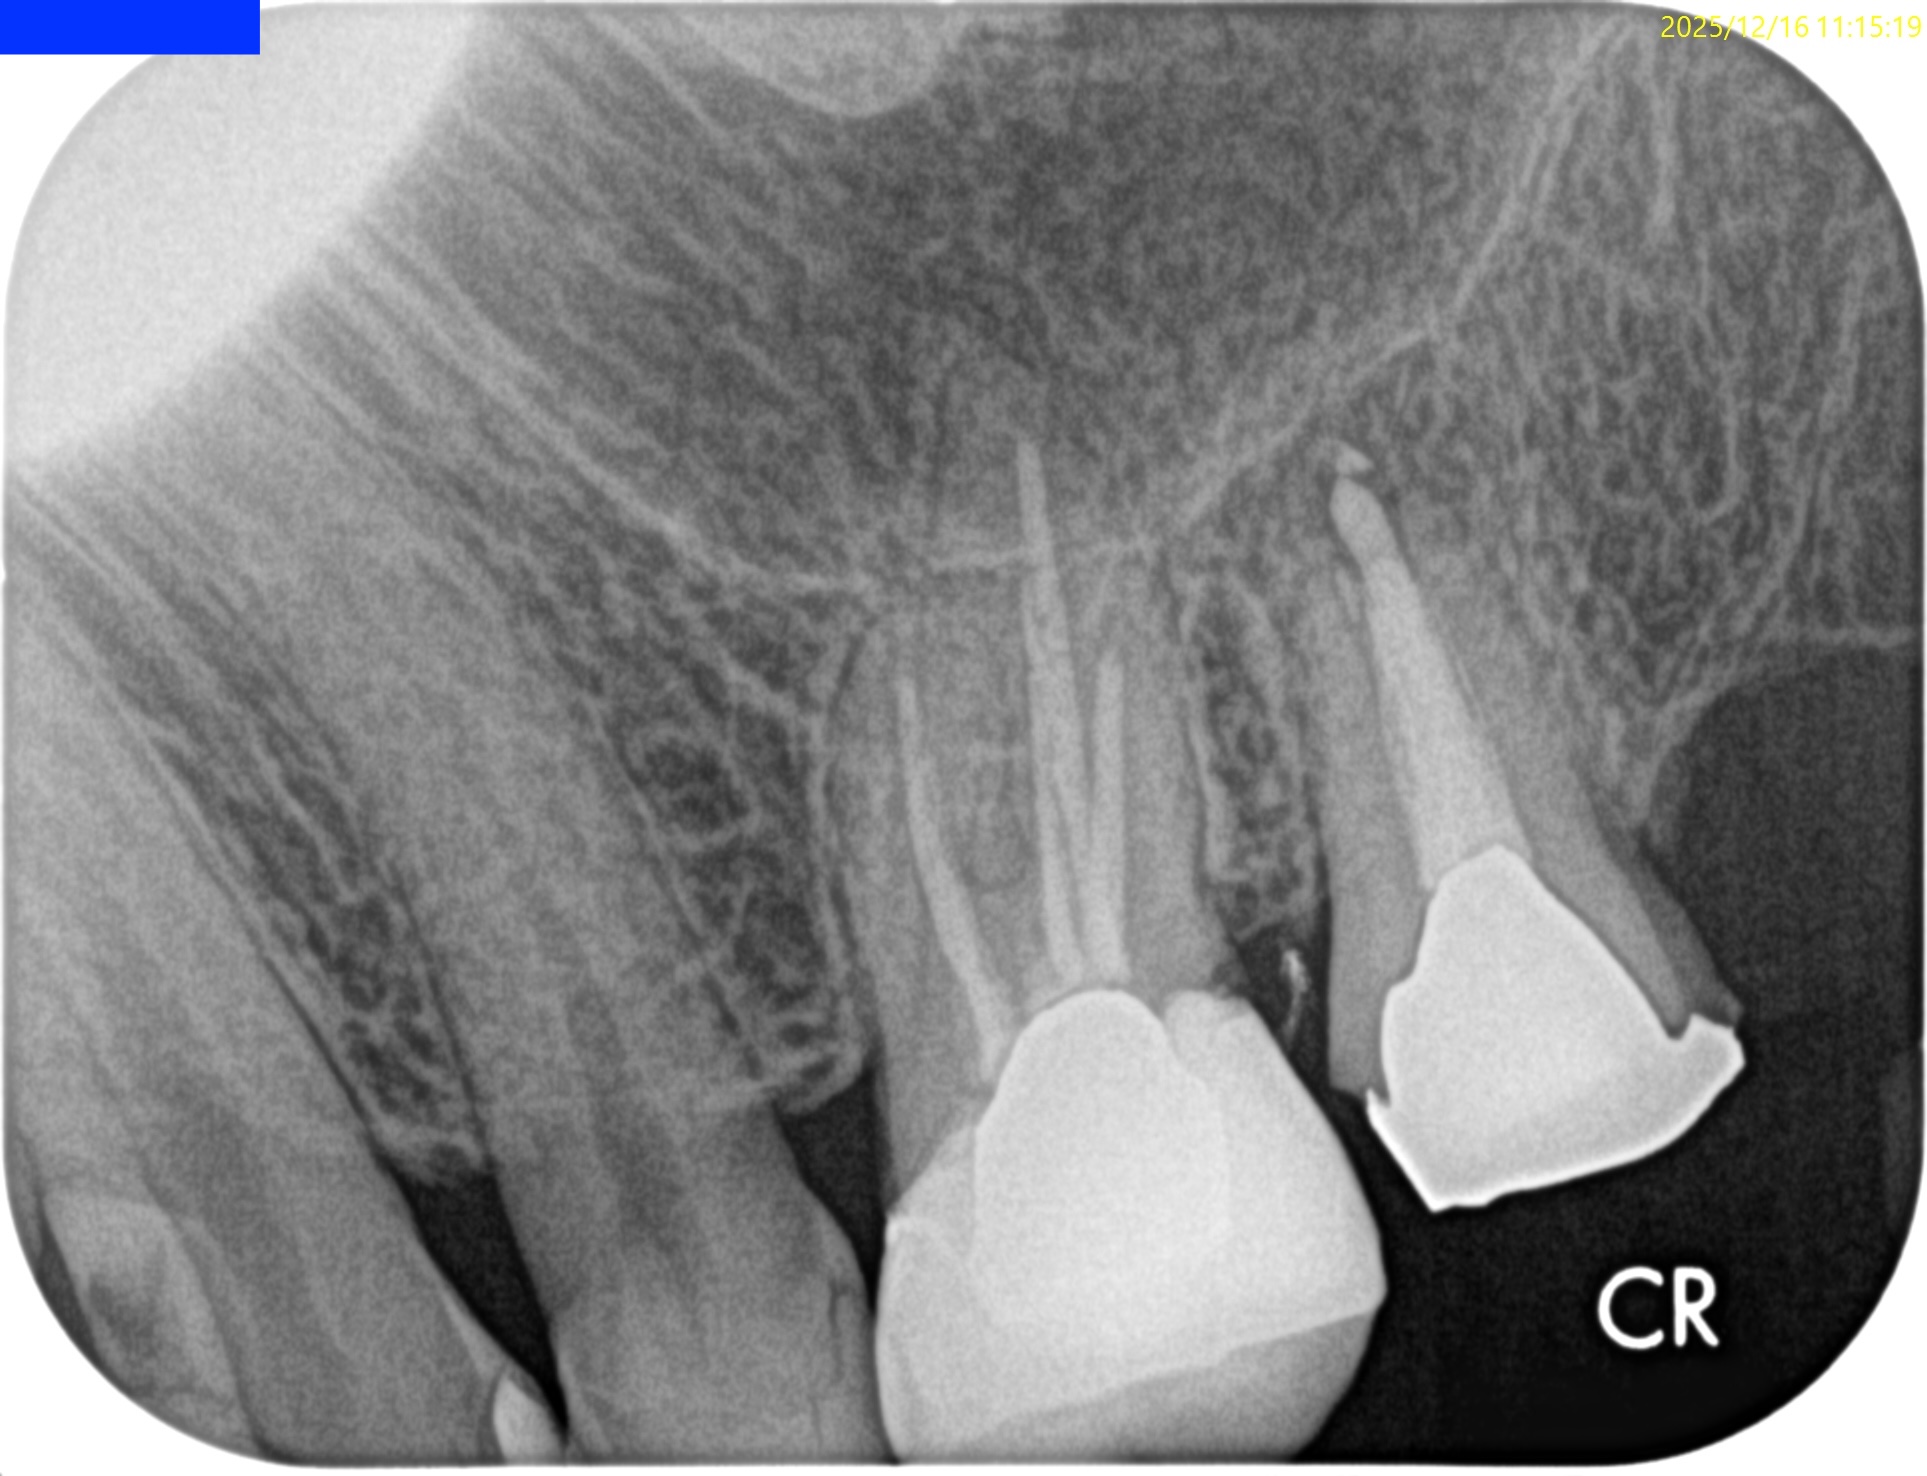

術後にPAを撮影した。

問題はないだろう。

術後にPA, CBCTを撮影した。